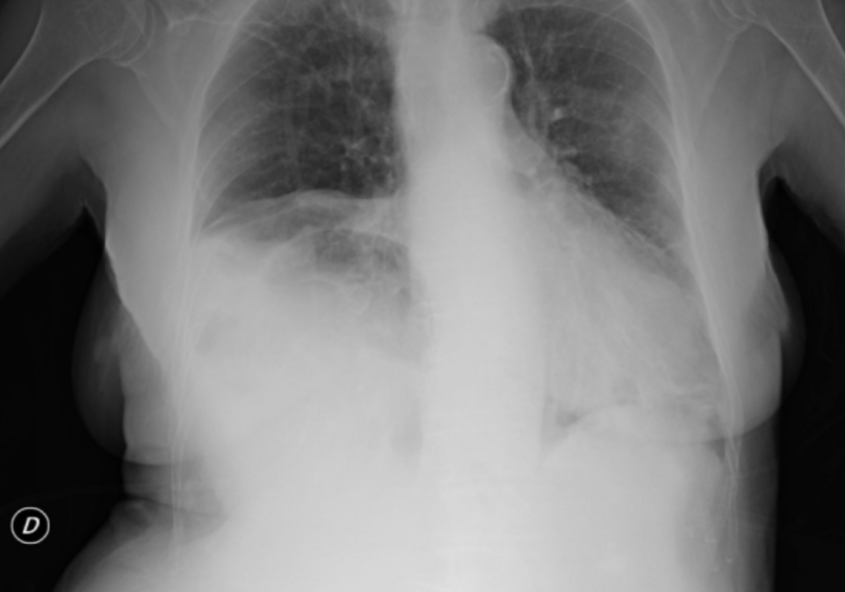

TERAPIA CON ANTI-ORMONI IN UN SUBDOLO CASO DI PNX CATAMENIALE

Lo pneumotorace (PNX) catameniale, l’espressione patologica più frequente dell’endometriosi toracica, è la patologia affrontata in questo articolo: attraverso l’analisi di un caso clinico, si giunge alla conclusione che la cura più indicata è la chirurgia con asportazione delle isole di endometriosi.